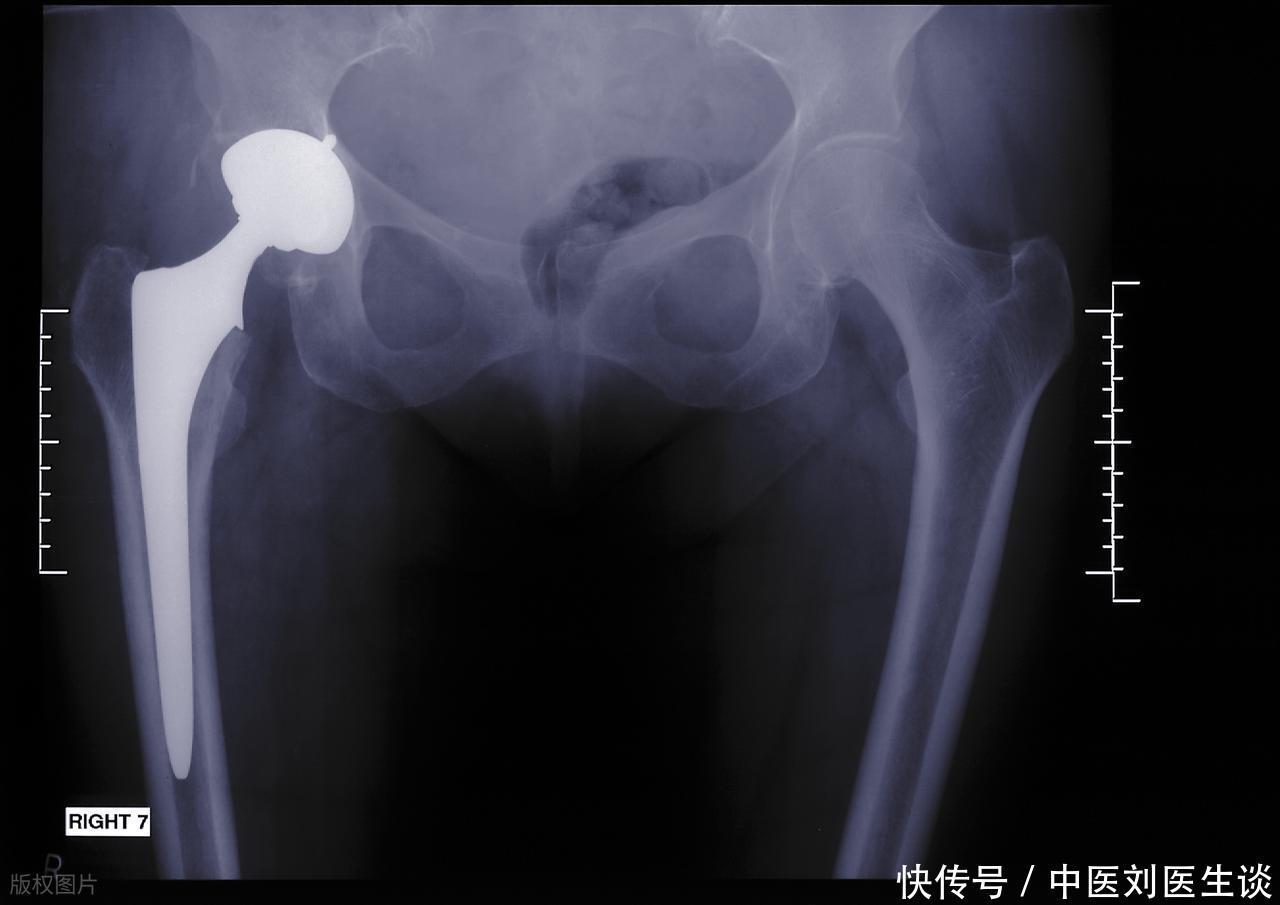

终于到了需要动刀子的时候,我们应该关注什么新变化?

如果经过充分的保守治疗,关节的结构性破坏已经到达了影响生活质量的那个临界点,手术便不再是“最后的手段”,而是“最合理的选择”。如今的手术理念强调“微创化”和“功能保留”。过去那种大开大合的入路已经越来越少见了,取而代之的是通过几个小孔,借助先进的器械和光学系统进行操作,这大大减少了对周围肌肉和软组织带来的创伤。这意味着术后的恢复速度被极大地压缩了,很多患者在术后不久就能开始早期活动负荷。